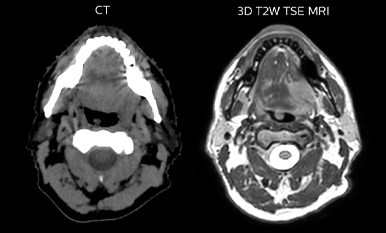

Comparison of CT simulation scan (left) and T2W 3D MRI (right)

MR-based target contouring on 3D T2W TSE in transversal, sagittal and coronal planes.